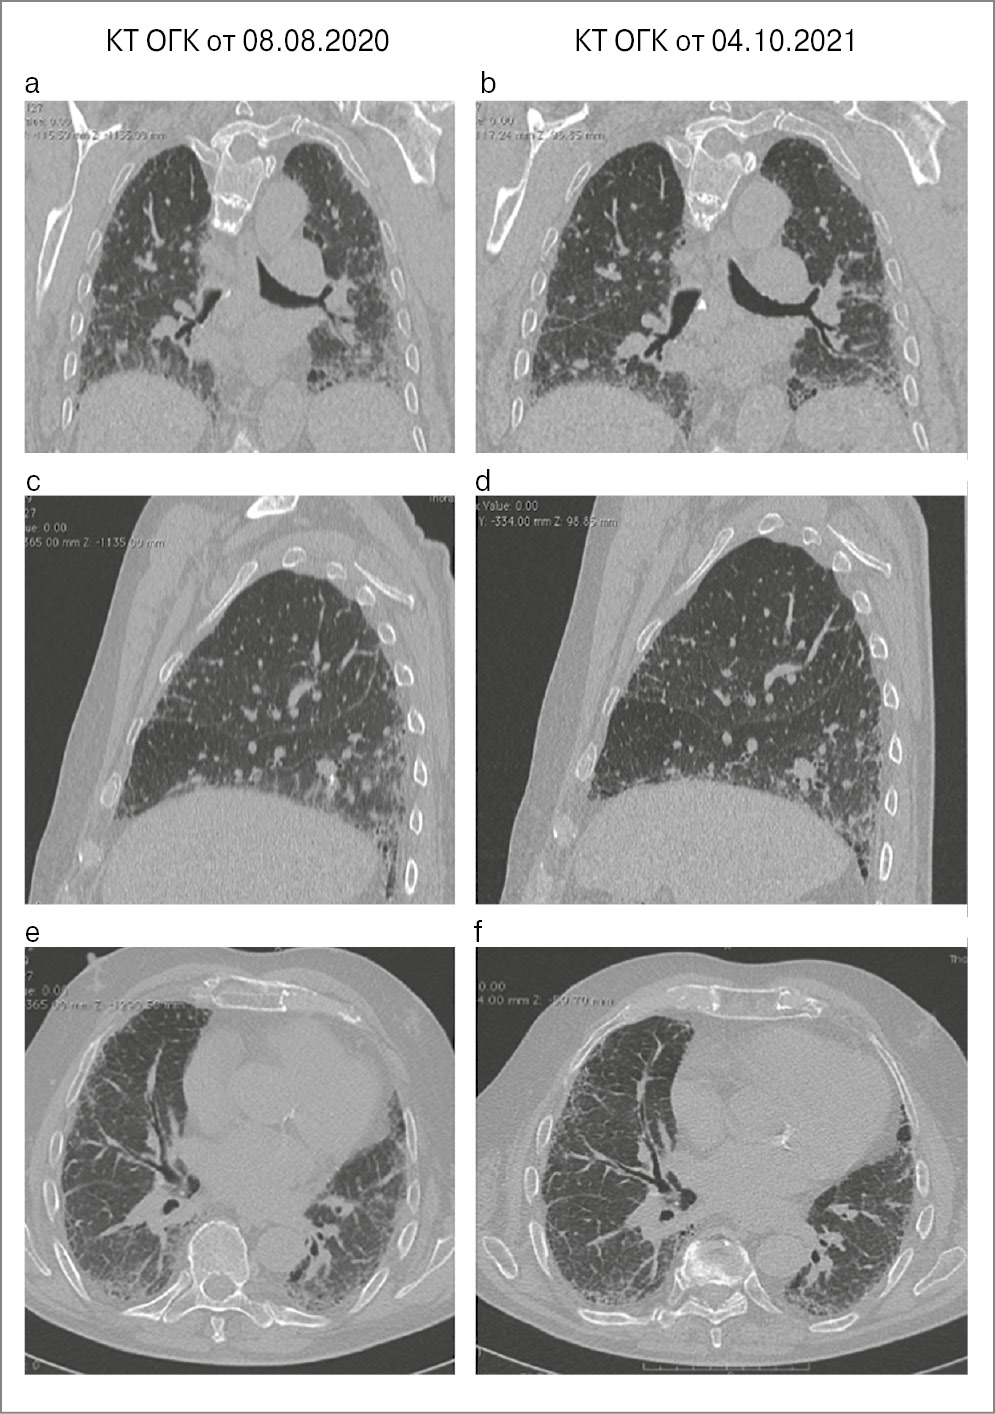

Август 2020 г. КТ ОГК (рис. 22): изменения по типу вероятной ОИП.

Рис. 22. КТ ОГК пациента Х от 28.08.2020.

КТ ОГК (рис. 23): КТ-паттерн вероятной ОИП – без динамики по сравнению с августом 2020 г.

Рис. 23. КТ ОГК пациента Х от 08.08.2020 в сравнении с КТ ОГК от 04.10.2021.